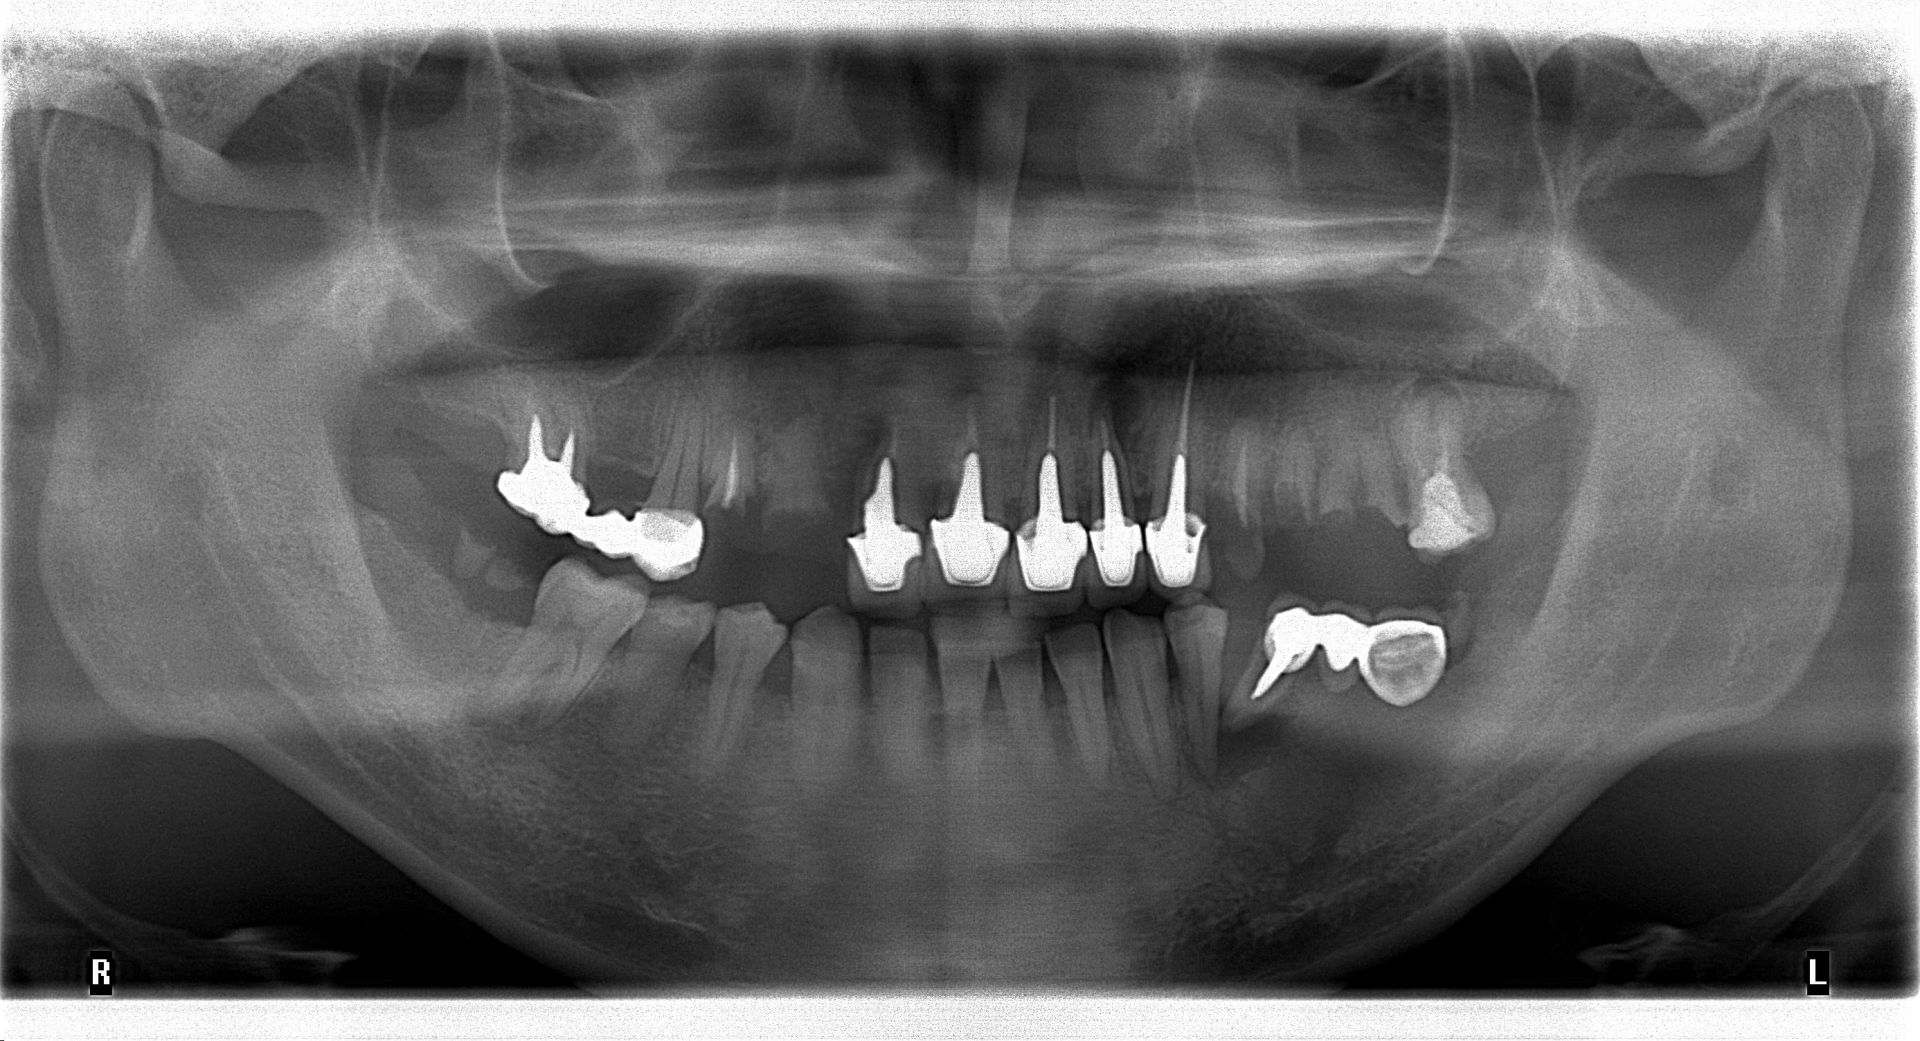

先行口腔內檢查,並結合環口式 X 光片與局部片作綜合判斷。

植體的分佈必須考慮到對咬牙的關係,影像中顯示,上下顎的植體位置精準對位,確保咬合力能垂直傳導至骨組織,避免植體鬆脫。